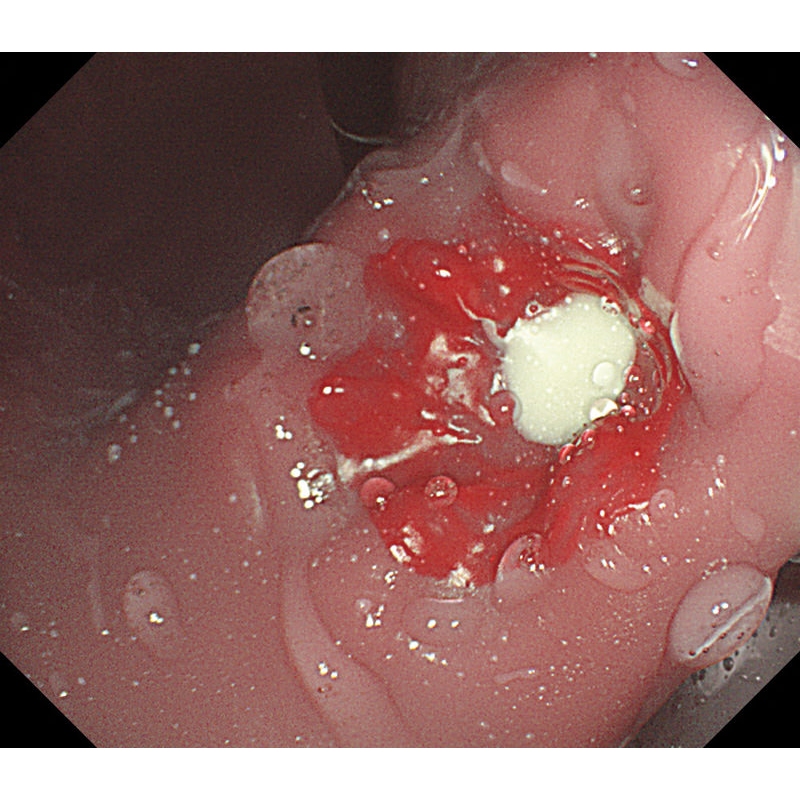

- V želodcu je mogoče opazovati želodčno razjedo in zgodnji rak želodca. Za opazovanje je mogoče pritrditi tudi štiri vrste polipov po Yamadovi klasifikaciji tipov od I do IV.

- V dvanajstniku je mogoče reproducirati razjedo.